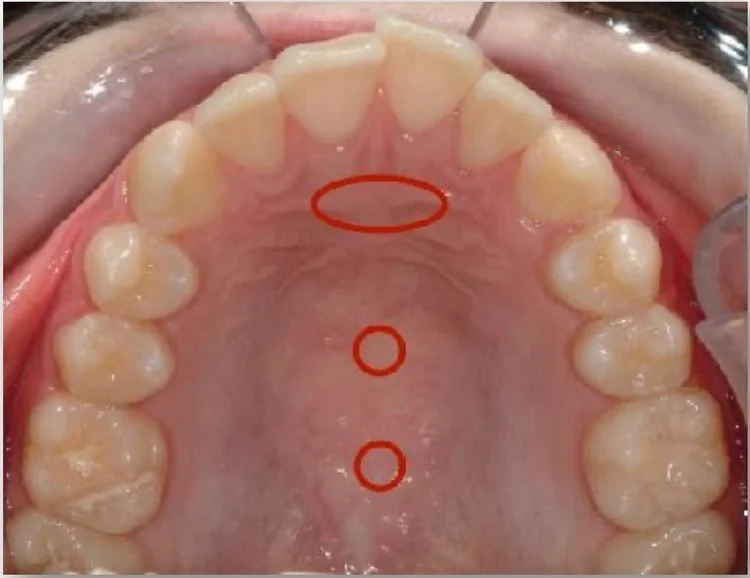

The tip of the tongue should rest on the “Spot”, which is right behind the incisive papilla, the ridge behind the front teeth (see oval red marking on photo). The lips should be closed at rest and nasal breathing should occur day and night.